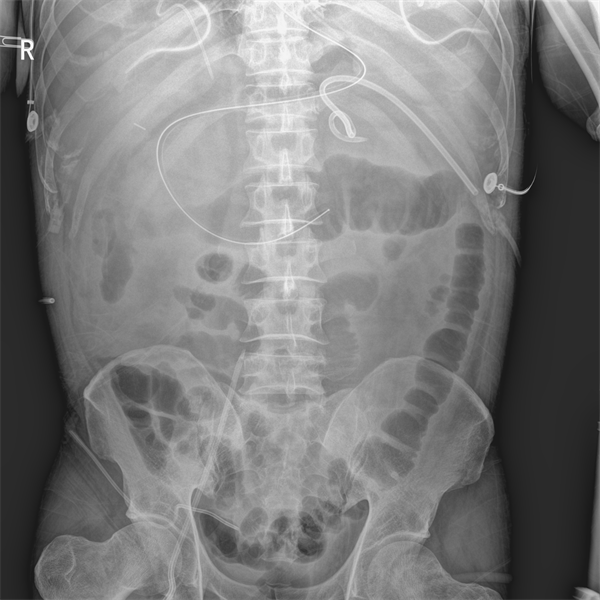

再者移动动态DR可以迅速为急诊患者建立管路通道提供动态透视环境。以“经外周静脉置入中心静脉导管(PICC)”为例,临床上使用床旁盲穿法置入技术,容易发生导管尖端异位的情况。有研究表明导管置入过浅,会增加功能障碍、纤维蛋白鞘形成,增加静脉血栓的发生风险;置管长度过深,会增加心律失常发生的概率。而使用移动动态DR就可以在床旁进行动态引导定位,引导导管正常走行,避免导管尖端异位或操作不当造成的并发症;同时对于血管畸形而造成的导管异位患者,可在动态影像下引导走行,能够有效提高导管复位的成功率。除了PICC,临床科室如ICU、肿瘤科、呼吸内科、感染科等都有不同疾病需要置管,那么这些需要置管的手术如PVC、CVC、PORT等就可以在移动动态DR上进行动态透视引导置管,相较于盲穿置管更精准、更安全、更高效率,同时还能避免患者转运带来的风险。

(患者插管影像图)